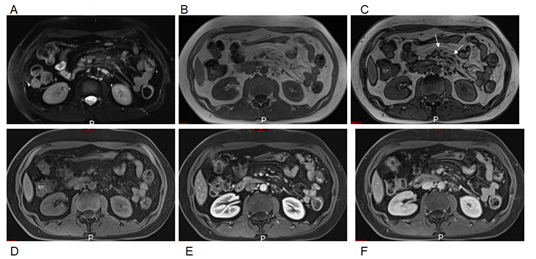

4. Severe disease (Figure 2). The dark duskiness of the mesentery is demarcated by a thick > 3 mm fibrous band. Multiple lymph nodes, many in the 1-2 cm size range. Lymph nodes extended beyond the affected region. Radiating fibrosis from the central core may be present. Bowel tethering is present.

Figure 2 Severe mesenteric panniculitis. Axial T1-weighted in-phase (A) and out-of-phase (B), pre-contrast (C), and interstitial phase (D) images. Out-of-phase images (B) exhibited the greatest clarity for depicting mesenteric panniculitis. On out-of-phase images, the mesenteric fat is mild gray in signal (arrows, B) and has definable margins with a thick fibrous band. Multiple lymph nodes are present. Note the increased enhancement of mesenteric panniculitis and adjacent jejunum over time.